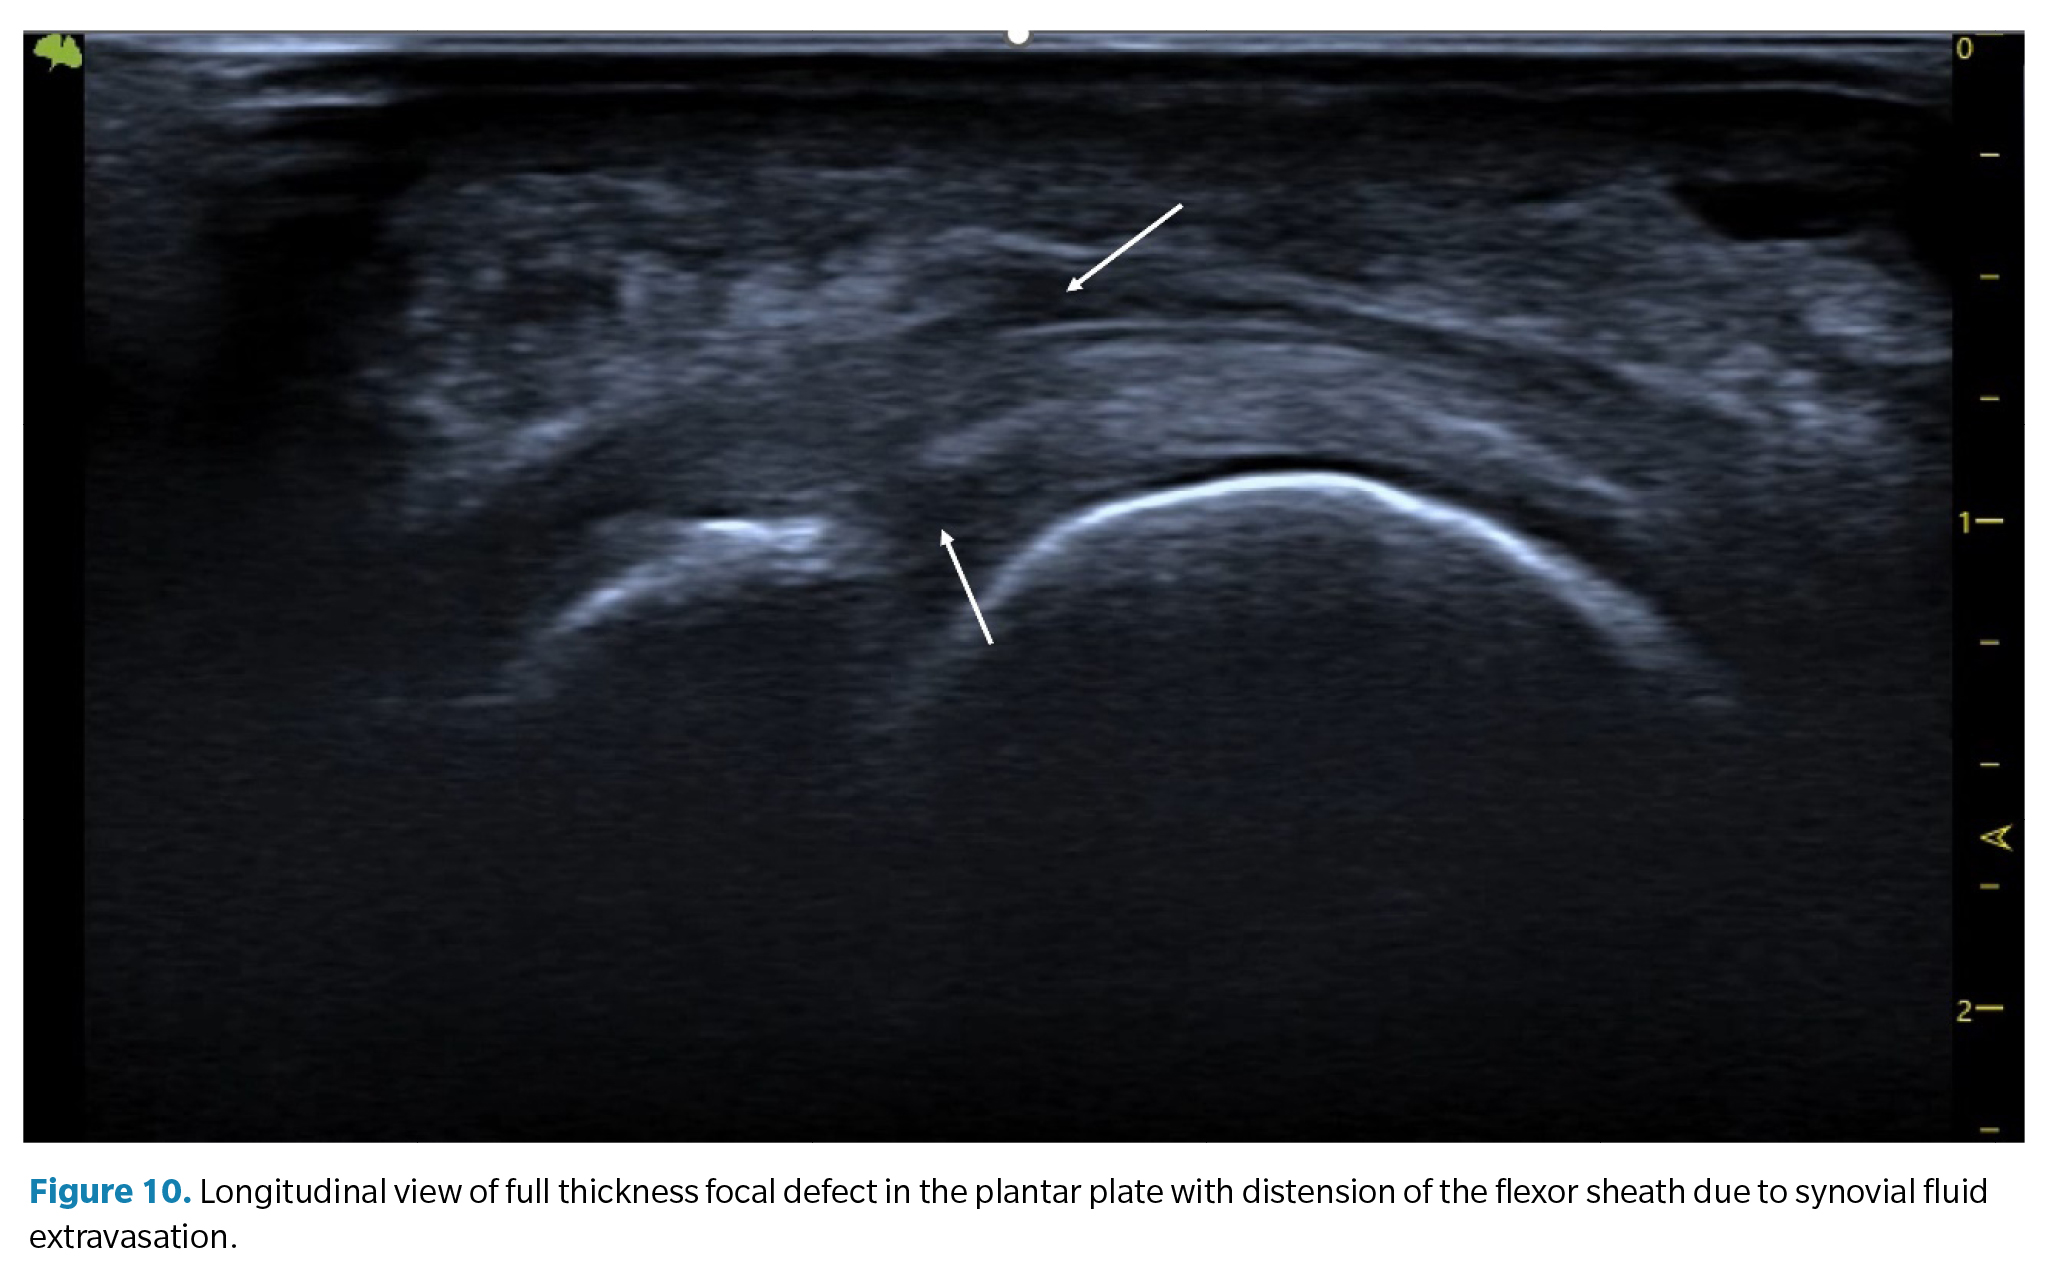

1. Plantar or dorsal joint fluid (synovitis). Synovial effusion. Since the plantar plate forms the plantar closure of the joint capsule, tears in the plate can lead to a significant increase in synovial fluid, which manifests as a detectable synovial effusion both dorsally and plantarly. In some cases, this fluid can leak into the flexor tendons, creating a hypoechoic halo around them resembling the characteristic image of tenosynovitis with distension of the tendon sheath (Figure 10).